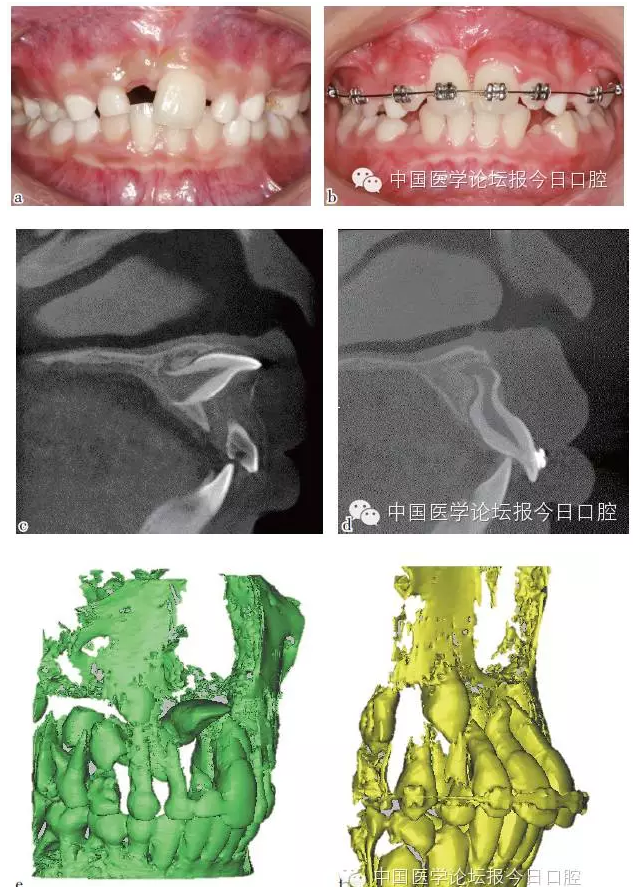

彎根牙的早期牽引助萌

先天及乳牙外傷導(dǎo)致繼承恒牙牙冠及牙根發(fā)育異常,臨床出現(xiàn)牙冠發(fā)育不全及彎根牙。

彎根牙的牽引助萌常受到彎根嚴重程度及彎根角度的影響,早期牽引能引導(dǎo)牙根形成方向,降低牙根彎曲的嚴重程度。

如病例二(圖2)所示,11彎根牙行早期牽引,11牙根繼續(xù)發(fā)育、彎曲程度減小。

圖2 11彎根牙行早期牽引;11牙根繼續(xù)發(fā)育,牙根彎曲程度減小